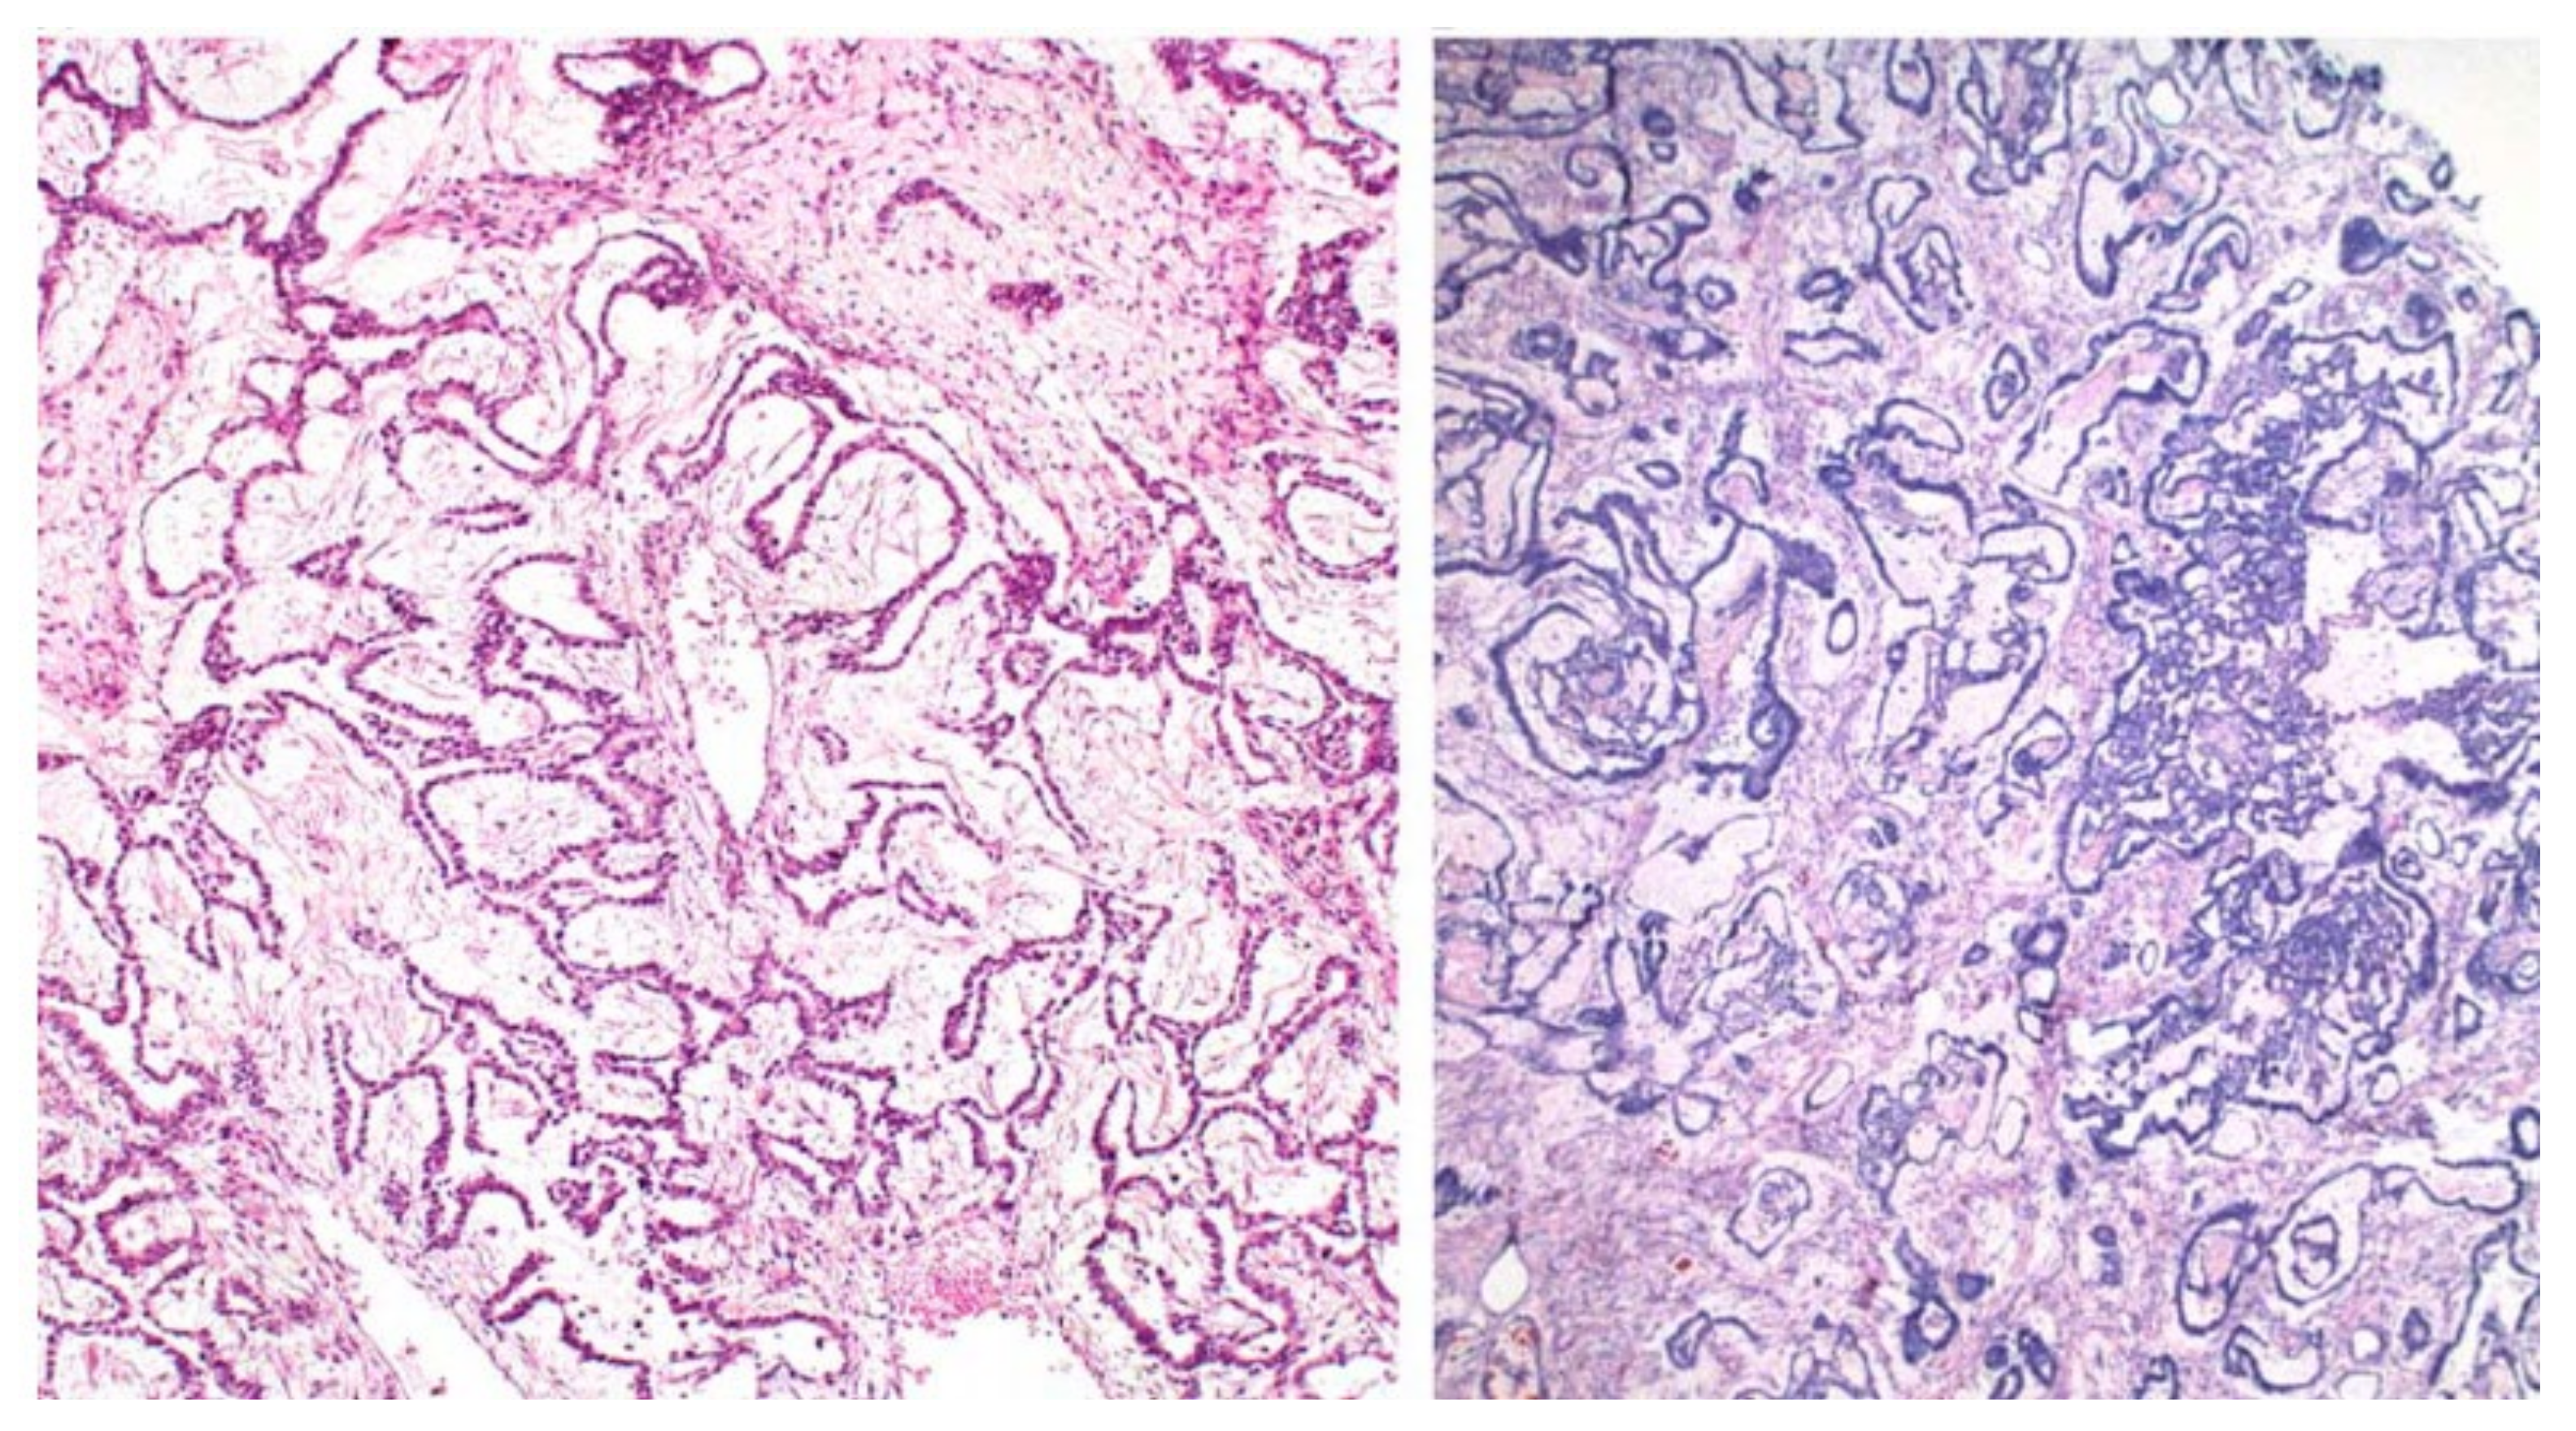

3.1. Ovarian GrCT

3.2. Sertoli-Leydig Cell Tumours